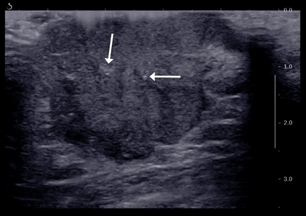

Figure 6 Ultrasound showing a large lobulated hypoechoic lesion at the right retro-areolar region with irregular margin. Multiple punctate calcifications seen within the lesion (white arrows).

A 74 years old gentleman with underlying hypertension and dyslipidemia presented to our Centre with a right breast swelling for the past 2 years. The patient claimed that the swelling been progressively increasing in size associated with bloody nipple discharge and foul smell. He never seeks any treatment since then. Clinically there was a (4x4) cm fungating mass at the right nipple-areolar complex (NAC), hard, non-tender and fixed to the underlying structures. The lesion demonstrated contact bleeding during manipulation. Mobile right axillary lymph nodes were palpable. A wedge biopsy was performed the next day and the histopathology result came out to be Invasive breast carcinoma, no special type (NST).Computed tomography (CT) of the thorax, abdomen and pelvis was arranged for the patient. It was reported as right breast mass with local extension to the underlying pectoralis major muscle with right axillary lymphadenopathy. Also reported was bilateral lung nodules which suggestive of metastasis (T4CN1M1). A right mastectomy with axillary dissection was performed, a total of 15 axillary lymph nodes were removed and sent for histological examination. Microscopic examination of the specimen was described as ductal carcinoma in-situ (DCIS) of high-grade nuclear feature comprising of cribriform and comedo-necrosis pattern. There were five out of seven lymph nodes positive for tumour infiltration. The patient was subsequently referred to the oncologist and a regime of six cycles of FEC (5-Fluorouracil, Epidoxorubicin, Cyclophosphamide) and 15 fractions of radiotherapy was planned (Figure 6, 7).